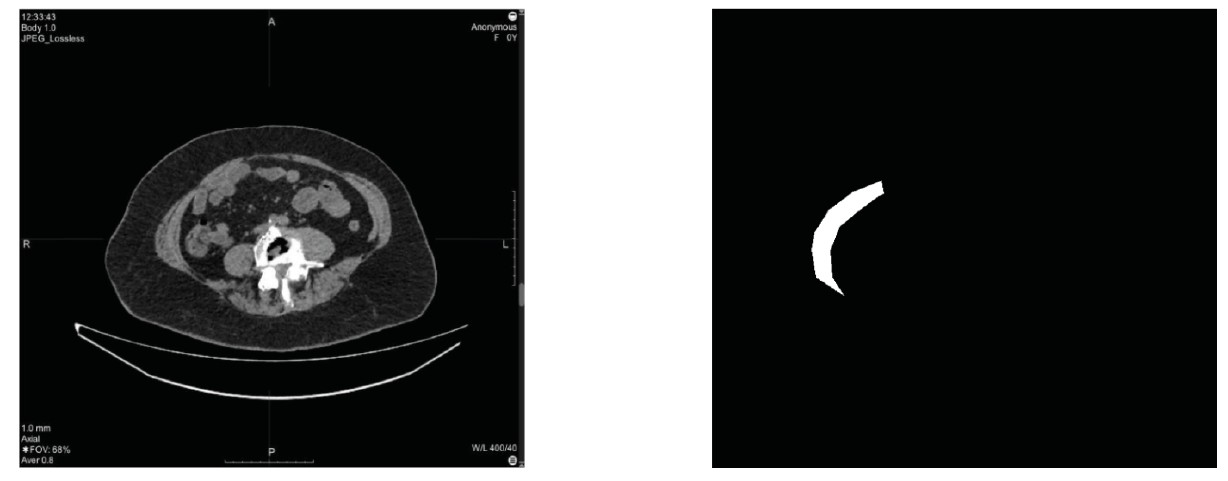

All patients underwent computed tomography (CT) of the thoracic cavity, abdominal cavity, and pelvic organs (three anatomical regions) (Figure 1).

Fig. 1. Example of a CT series in the axial projection for segmentation

For analysis, three independent groups were formed: group 1 (N=30): patients without postoperative ventral hernias (POVH) who were examined or treated for unrelated chronic pathology. Group 2 (N=30): patients diagnosed with W2 POVH. Group 3 (N=30): patients with large or giant ventral hernias (W3), who were candidates for preoperative botulinum therapy before surgical intervention.